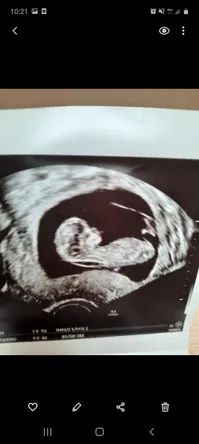

Clarté nucale 4 mm clarté nucale a 42mm Amniocentèse FORUM Grossesse 1ere echo 11 sa et 3 jrs, clarté nucale 42 mm!

La mesure de l'épaisseur de la clarté nucale permet de déterminer un risque d'anomalie chromosomique chez le fœtus trisomie 21, mais aussi trisomie 13 et 18 " Plus cette épaisseur est augmentée, plus le risque que le bébé soit trisomique est augmenté ", informe le radiologue " Une clarté nucale épaisse avec un caryotype normal Voilà, vendredi dernier je passe ma T1 et le gynéco nous annonce une clarté nucale anormale et plutôt épaisse (3,11mm), il m'oriente donc sur la pds tri test dès l'aprèsmidi Le médecin m'appelle lundi pour me donner les résultats très mauvais, je suis dans les cas à risques très élevés (1/14)